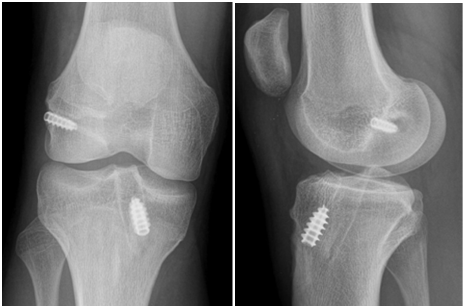

Tiếng lạo xạo khi cử động khớp gối thường hay gặp ở những bệnh nhân sau mổ, nó thường lành tính, có thể giải quyết được bằng cách tập luyện phục hồi chức năng.

Tiếng lạo xạo khi gấp, duỗi sau mổ là hiện tượng khá thường gặp (18% bệnh nhân sau mổ). Tuy nhiên, nếu vấn đề này kéo dài, các bác sĩ có thể khuyến cáo một số thủ thuật nhỏ để gỡ dính xung quanh khớp.

Một lý do khác cho tiếng lạo xạo là dính khớp hoặc các mô xung quanh bị xơ hóa, điều này có thể dẫn đến cứng khớp và gây đau khi vận động, cử động khớp gối.